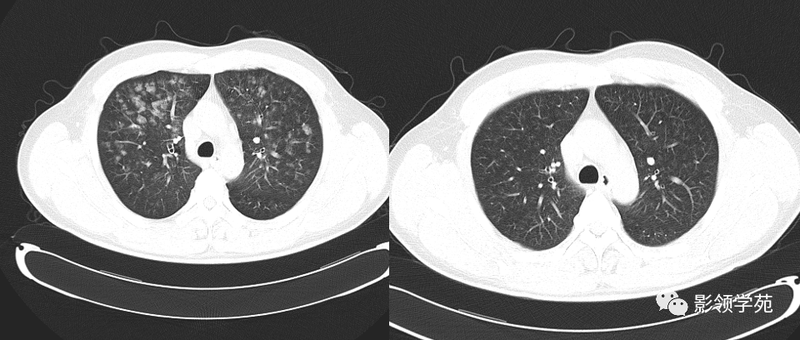

(5)肺内多发结节,由肉芽肿和炎症构成,较大结节发生空洞,多数结节边缘见有血管进入,则要考虑到肺韦格氏肉芽肿可能。

熟悉掌握肺部基本病变的CT表现,是诊断肺部疾病的基础,要仔细观察CT片上所呈现的各种表现,发现其特点,并对这种CT特点与病理表现的相互联系有清楚的理解,以便准确解释CT检查所包含全部信息和细微差别,要特别注意是相同疾病,不同表现,不同疾病,相同表现,要求我们必须密切结合临床症状及各种实验室检查指标,对每一个CT特征进行仔细的分析与鉴别,做出较为准确的诊断结果。